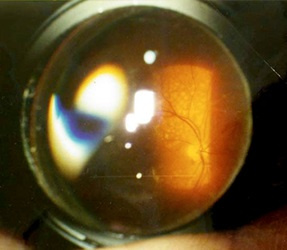

By the way, for inspection, you need to use not a flashlight, as is done in most clinics, but special lenses for examining the fundus. There is a universal contact lens — Goldman's lens. This flat lens with a system of three mirrors is very widely used in the examination and laser coagulation of the anterior segment of the eye and retina.

顺便说一句,进行检查时,您不需要像大多数诊所那样使用手电筒,而是需要使用特殊的镜片检查眼底。 有一个通用隐形眼镜-高盛镜头。 这种带有三面镜系统的平面透镜非常广泛地用于检查眼和视网膜的前段并进行激光凝结。

In each mirror, we see different parts of the retina, and, turning it clockwise, we get complete information. Something like this:

在每个镜子中,我们都可以看到视网膜的不同部分,顺时针旋转它可以获取完整的信息。 像这样:

And this is the scheme in which mirror which department of the eye we inspect:

这是我们检查哪个眼部的方案: